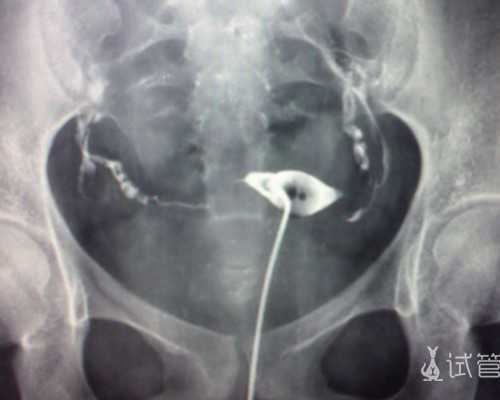

1、卵子冷冻技术是近些年来才取得成功并运用于临床辅助生殖的一项技术,是将卵子从体内取出并通过冷冻的方式保存年轻状态下的健康优质卵子,以延长女性的最佳生育年龄,待想生育时再将进行解冻,然后通过“体外受精胚胎移植”的试管助孕途径来达到受孕目的。

2、选择冻卵的女性,根据需求可将卵子冷冻保存5年、10年甚至更久,这意味着在五年、十年后想生育的您卵子质量还保留在冷冻时的年龄,避免了随年龄增长,卵子质量下降或老化容易发生染色体异常、胎停、流产及畸形儿等情况,使其真正从传统的家庭、事业难以两全的尴尬境地中解救出来。

6、此次受赠16颗成熟卵子,养成7颗囊胚,PGS/PGD检查后显示有3颗正常,2女1男。